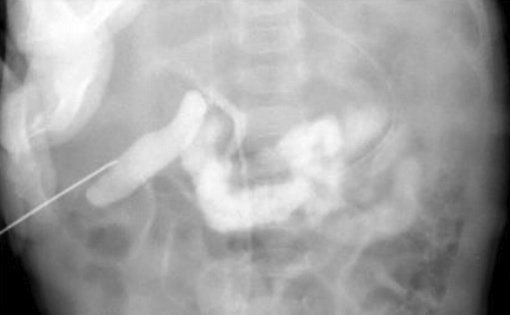

Для диагностики синдрома сгущения желчи используется также и интраоперативная холангиография через пунктированный желчный пузырь, позволяющая выявить полную обструкцию общего желчного протока с дилатацией пузырного протока и печеночного протока (рис. 4).

Рисунок 4. Синдром сгущения желчи. Чрескожная холецистохолангиография через пунктированный желчный пузырь. Дилатация и обрыв общего желчного протока и умеренная дилатация интрапеченочных желчных протоков [24, 25]

Figure 4. Bile thickening syndrome. Percutaneous cholecystocholangiography via a gallbladder puncture. Dilatation and rupture of the common bile duct and moderate dilatation of the intrahepatic bile ducts [24, 25]

Терапия синдрома сгущения желчи у детей раннего возраста включает хирургические и консервативные методы. В оперативном лечении, позволяющем восстановить пассаж желчи в двенадцатиперстную кишку, нуждаются менее 4% детей с синдромом сгущения желчи (рис. 4). Исторически первым хирургическим вмешательством была лапаротомия с последующей ирригацией через доступ в общий желчный проток или желчный пузырь, выполненная W.E. Ladd в 1935 г. [7, 26].